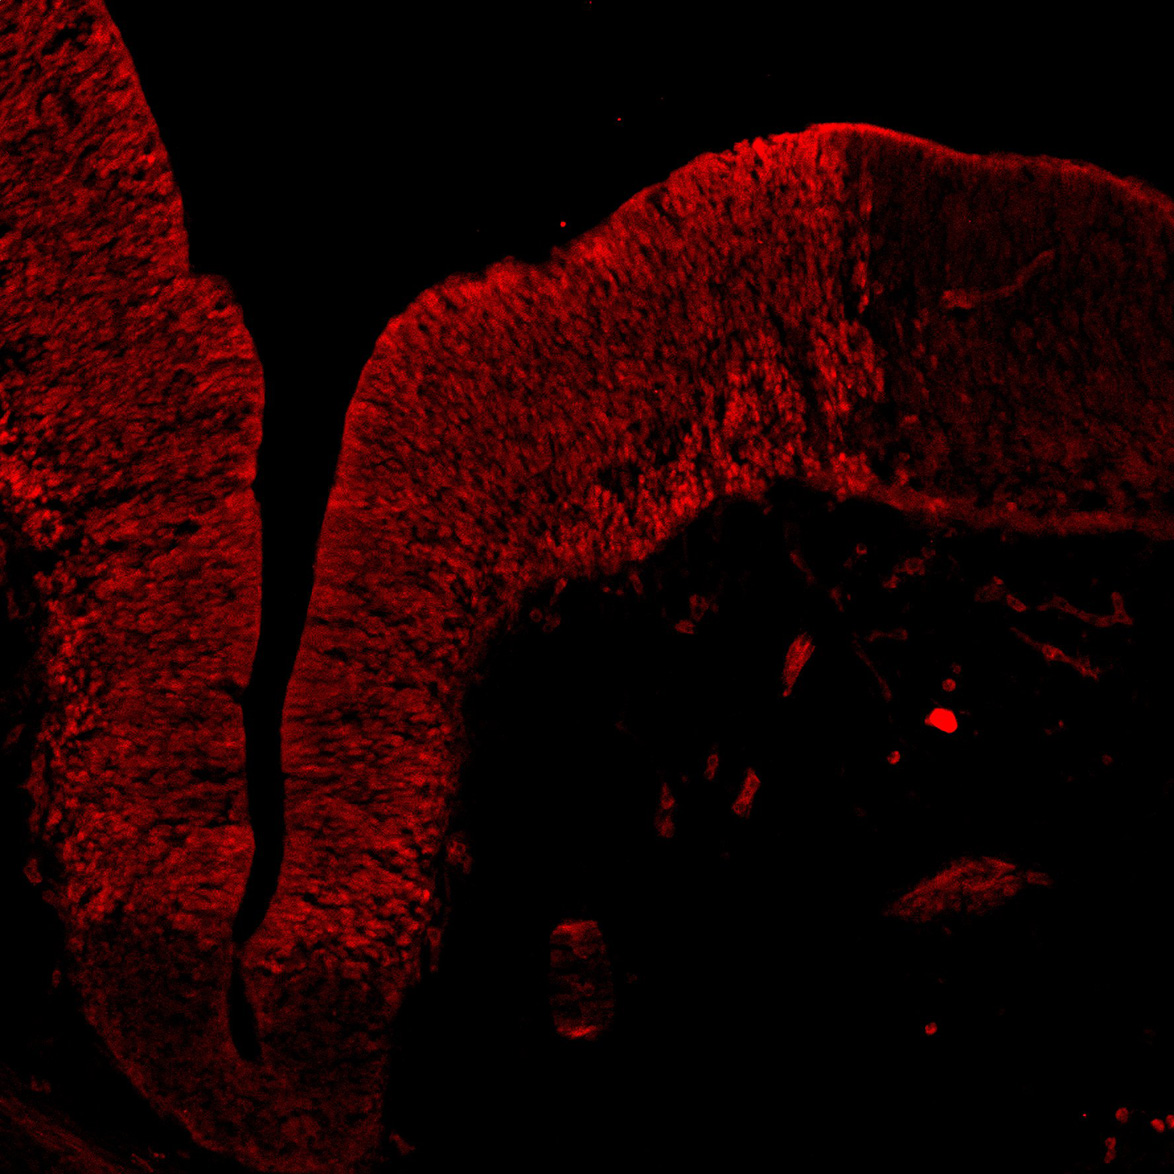

An anatomical analysis of the developing human midbrain from 6 post-conceptional weeks (PCW) to 22 PCW reveals increased tissue complexity, characterized by the emergence of dopaminergic nuclei, as highlighted by immunofluorescence analysis for tyrosine hydroxylase (TH).

TH

11PCW human midbrain